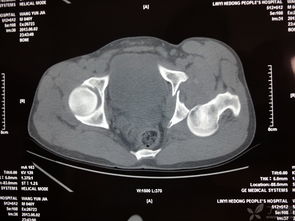

髖臼骨折,恥骨骨折,經(jīng)檢查無需住院,2回答者:lianghuanjie